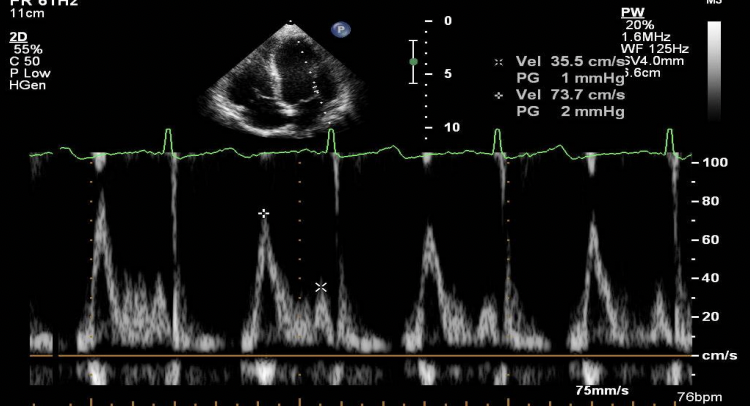

Hình 10. Hình ảnh siêu âm Doppler xung dòng chảy van hai lá

+ Dòng van hai lá: ghi tốt nhất ở mặt cắt 4 buồng từ mỏm tim.

- Thời kỳ tâm trương: hai sóng dương, bao gồm sóng E (sóng đổ đầy đầu tâm trương của thất trái) và sóng A (sóng đổ đầy khi nhĩ trái co bóp).